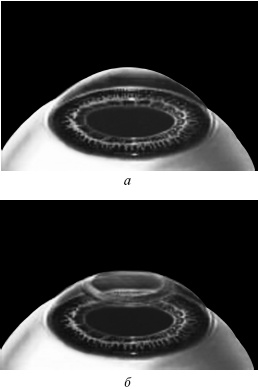

Ждем, когда закончится приживление лоскута к ложу. Эпителий цел и невредим. А значит, никаких болей. Около трех часов возможны слезотечение и светобоязнь. И все (рис. 9).

Рис. 9. Форма роговицы до проведения коррекции (а) и после коррекции близорукости (б). Испарение нескольких микрон толщины роговицы привело к уменьшению ее кривизны в центре.

Иллюстрация с сайта Международного лазерного центра www.optics.ru